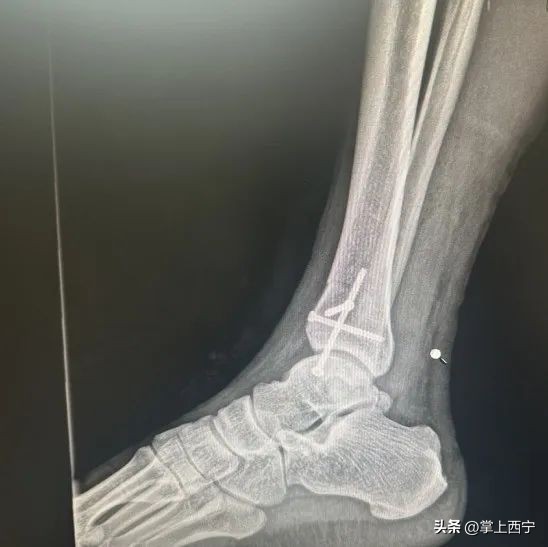

↑ 术前X射线平片

经过骨二科鲍义章主任和医师团队的进一步诊察,诊断为距骨软骨损伤并收治入院。患者入院后,医护人员为患者进行了充分的术前检查,经科室医师团队进行周密的病例讨论后,完善了各项术前准备,为患者施行了自体骨软骨移植术治疗距骨软骨损伤。

术中全生炳医师和于贵鑫医师熟练地进行取距骨前方非负重区正常带软骨帽骨柱,取内踝部分松质骨,将松质骨及骨柱植入坏死区,透视见病灶清除彻底,关节面平整满意,手术过程非常顺利。